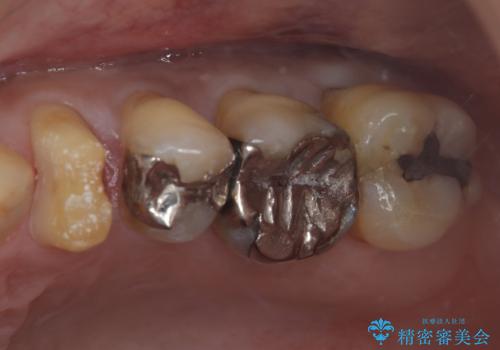

- 治療計画

- 当院で矯正後徐々にセラミックにやり替えたいとのことで来院された患者様です。レントゲン撮影の結果、メタルインレーの不適合を認めました。またメタルインレーの範囲も大きくご自身の残せる歯の量を考慮してオールセラミッククラウンによる補綴治療を行っていくことにしました。

拡大鏡視野下でメタルインレー、虫歯を除去しオールセラミッククラウンに適した形に整えました。